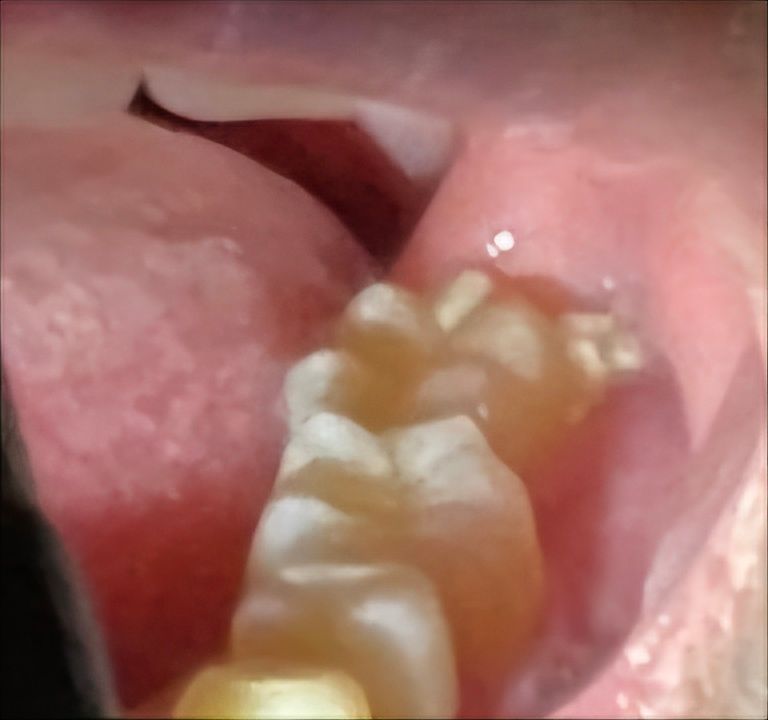

사랑니 발치 후 노란 찌꺼기는 뭔지 궁금해요

사랑니 발치하고 3주 좀 안됐는데 사진보다 좀 더 찌꺼기 느낌으로 있어요 양치도 열심히하고 물가글도 하는데 음식물은 다빠지고 쟤만 안빠지네요 ㅠㅠ 원래그런가요?

• 1번 째 사진

사랑니 발치를 3주정도에 하셧는데 아직 잇몸이 다 아물지 않아서 음식물이 껴 잇는거 같습니다. 제거가 안되면 치과에 가셔서 제거를 해달라고 하세요.

노란색 물질이 무엇인지는 알기 어렵습니다. 음식물이나 이물질일 것 같으며 저절로 빠질겁니다.

사랑니 발치후 찌꺼기 같이 남아있는 것이 보이는 경우 상처가 치유되는 과정에서 발생할 수 있는 혈전이나 잔여 조직일 가능성이 높습니다. 발치 부위를 너무 세게 문지르지르거나 하지는 말고 소금물이나 헥사메딘 가글액으로 가글을 하여 관리하길 권합니다.

만약 찌꺼기가 지속적으로 남아 있거나 통증, 붓기, 열감이 동반시에는 치과 진료를 받길 권합니다.